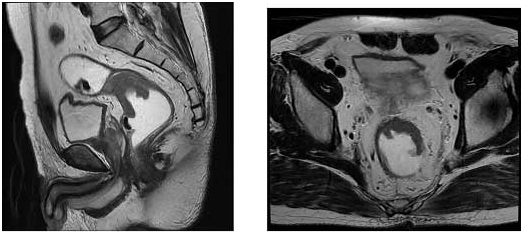

[실제 직장암 환자에서 MRI 소견]

좌측의 사진은 직장을 옆에서 잘라 본 영상이고, 우측의 사진을 직장을 횡단면으로 잘라서 본 영상입니다. 직장의 앞 벽에 궤양을 동반한 침윤성 종괴가 보이고 있어 직장암에 합당한 소견입니다. (화살표) 직장암의 침범 범위는 직장벽을 뚫고 주변 조직으로 침윤하고 있어 국소 진행성 병기(T3)의 직장암임을 알 수 있습니다. 이와 같이 MRI 검사는 여러 방향에서 바라 본 영상을 제공해 줄 수 있고, 조직간의 대조도가 뛰어나다는 장점으로 인해 정확한 진단 뿐만 아니라 직장암의 범위를 정확히 알게 함으로써 환자에게 적합한 치료 방침을 결정하는데 큰 도움이 됩니다. 이 환자의 경우에는 수술 전 항암방사선화학요법으로 직장암의 침범 범위를 줄인 후에 수술을 시행 받았습니다.